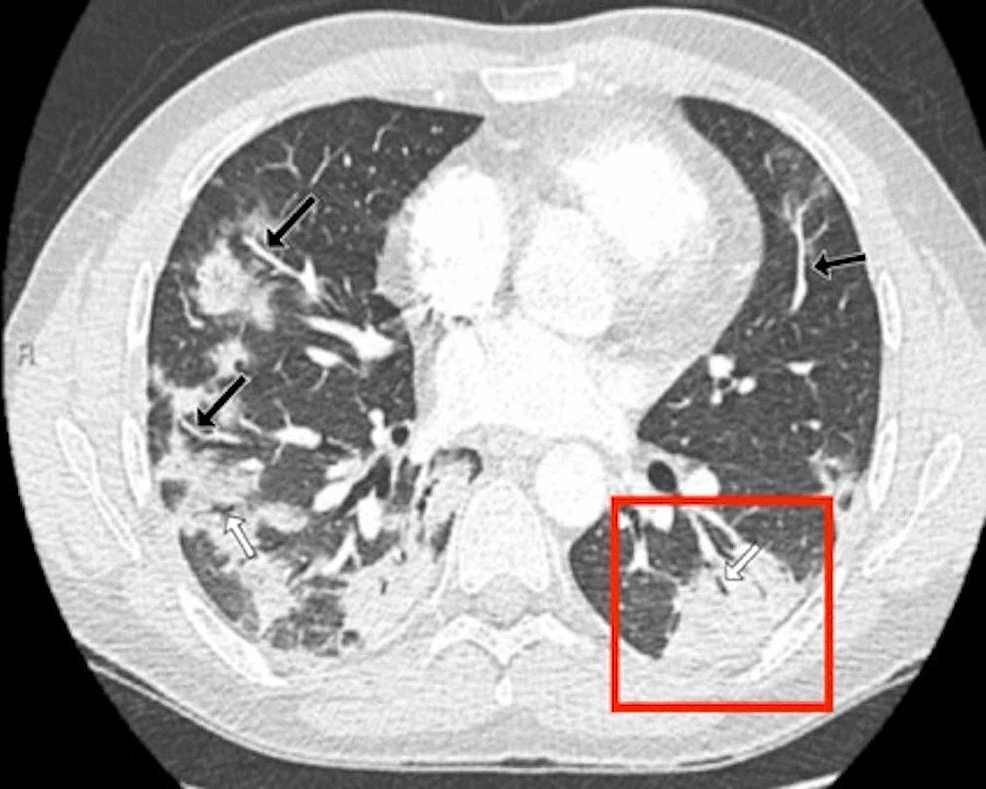

The distinctive CT features in our cohort are summarized in Table 3, including GGO and consolidative patchy mostly amorphous (72%) lesions, bilateral posterior and peripheral multi-lobar lung involvement, pleural effusions, subpleural fibrotic lines, subpleural sparing, vascular engorgement, occasional crazy paving, occasional mediastinal lymphadenopathy, pleural thickening, lack of cavitation, and absence of reverse halo (atoll) signs.

Subpleural sparing, which was observed in this patient cohort, has never been reported before, whereas mediastinal lymphadenopathy has been reported occasionally in the literature in English [11]. Focal vascular engorgement, septal thickening, and a subpleural fibrotic line were seen frequently in our cohort, with frequencies of 83%, 72%, and 61%, respectively.

Patients’ CT features are presented in detail in Figures 3, 4, 5, 6, 7, 8. A majority of cases (56%) had moderate severity scores. There was no correlation between the severity score and mortality, p=0.790 (Table 4).